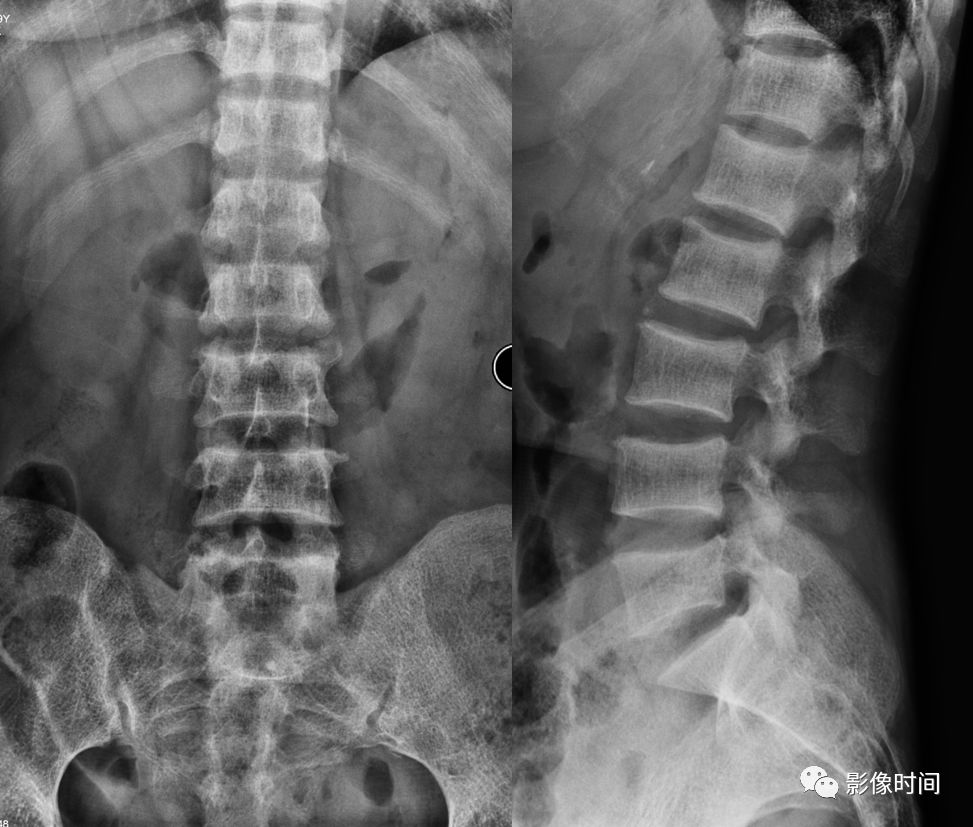

26夹心蛋糕征与橄榄球衫椎

前言:夹心蛋糕及橄榄球衫椎均用于描述椎体,上下终板区域带状密度增高,而中心区域密度相对低,高低密度区间杂。部分同道可能会混用,但两者有所不同,查询国内外书籍、文献及网页,总结如下:中文书籍中的所谓「夹心蛋糕征」,主要用于描述石骨症(也称骨硬化症),与英文「Sandwich vertebral body」(三明治椎体)对应,而橄榄球衫椎(Rugger-jersey spine)主要用于描述甲状旁腺功能亢进(原发及继发),国内主要用于描述肾性骨病,继发甲状旁腺功能亢进。

两者表现类似,区别在于三明治椎硬化带密度更高,边界更清晰,而橄榄球衫椎硬化带边界不够清楚,也没有那么致密(注:确实有混用情况,但大部分如上所说)。

典型病例

病例 1,石骨症。腰椎正侧位片示腰椎椎体上、下终板区域显著硬化,而中央区密度较低,呈夹心蛋糕征/三明治椎体。

病例 2,69 岁女性,肾性骨病。视野内诸骨密度不均匀增高,骨小梁模糊。腰椎椎体上下终板区域密度增高,中心区域密度较低,边界不清,呈「橄榄球衫椎」表现。